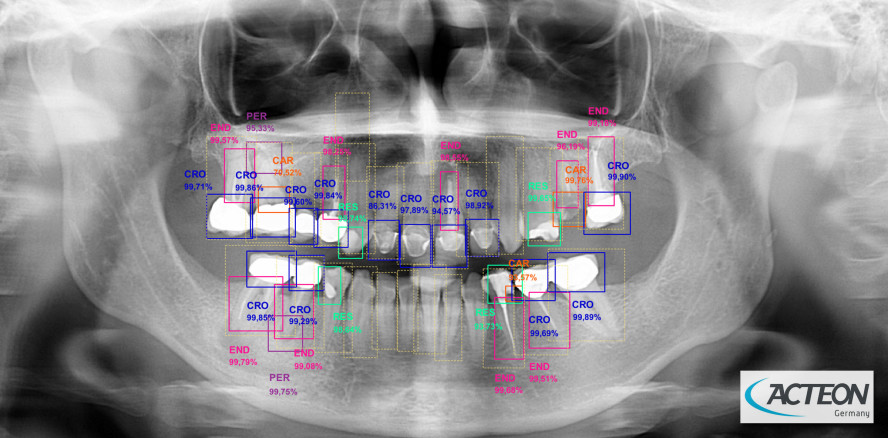

Als einer der Innovatoren auf dem globalen Markt für die zahnmedizinische Bildgebung hat ACTEON® künstliche Intelligenz in sein Bildgebungsangebot integriert. Das Programm für computergestützte Diagnostik ist demnächst in der intuitiven Software ACTEON Imaging Suite (AIS) aller 2D- und 3D-Bildgebungsprodukte enthalten.

Die AIS-Software analysiert die Bilderfassung sofort und hebt klinische und pathologische Elemente hervor. So unterstützt AIS Zahnärzte bei ihren Diagnosen und Behandlungsempfehlungen erheblich und hilft, die Kommunikation mit den Patienten zu verbessern.

Mit dem maschinellen Lernen in AIS werden Erkrankungen und frühere Behandlungen sofort erkannt und durch farbige Rechtecke auf dem Bild dargestellt. Zudem wird die Auswertung des Zahnzustands aufgezeigt. Insbesondere werden drei Arten von Erkrankungen und Behandlungen hervorgehoben: Anomalien (Karies, apikale Parodontose, Kronen, endodontische Behandlungen, Implantate, Zysten, Zahnstein, Verschleiß, Abutment und Restaurierung), Bereiche mit hohem Knochendichteverlust sowie Parodontalerkrankungen.

Auf diese Weise unterstützt der maschinelle Lern-Algorithmus Zahnärzte bei der Diagnose und erleichtert die klinische Entscheidungsfindung. Nicht zuletzt ist die visuelle Darstellung von Erkrankungen ein praktisches Werkzeug für die Kommunikation mit Patienten in Bezug auf deren Behandlung.